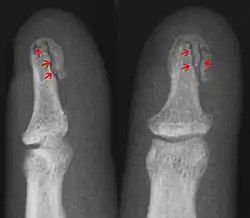

Radiography to identify possible fractures after a knee injury

A bone fracture may be diagnosed based on the history given and the physical examination performed. Radiographic imaging is often performed to confirm the diagnosis. Under certain circumstances, radiographic examination of the nearby joints is indicated to exclude dislocations and fracture-dislocations. In situations where projectional radiography alone is insufficient, Computed Tomography (CT) or Magnetic Resonance Imaging (MRI) may be indicated.